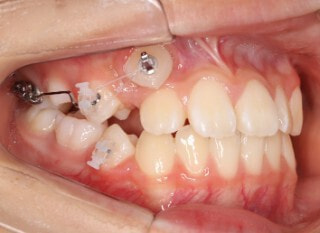

治療前

前歯装置装着時